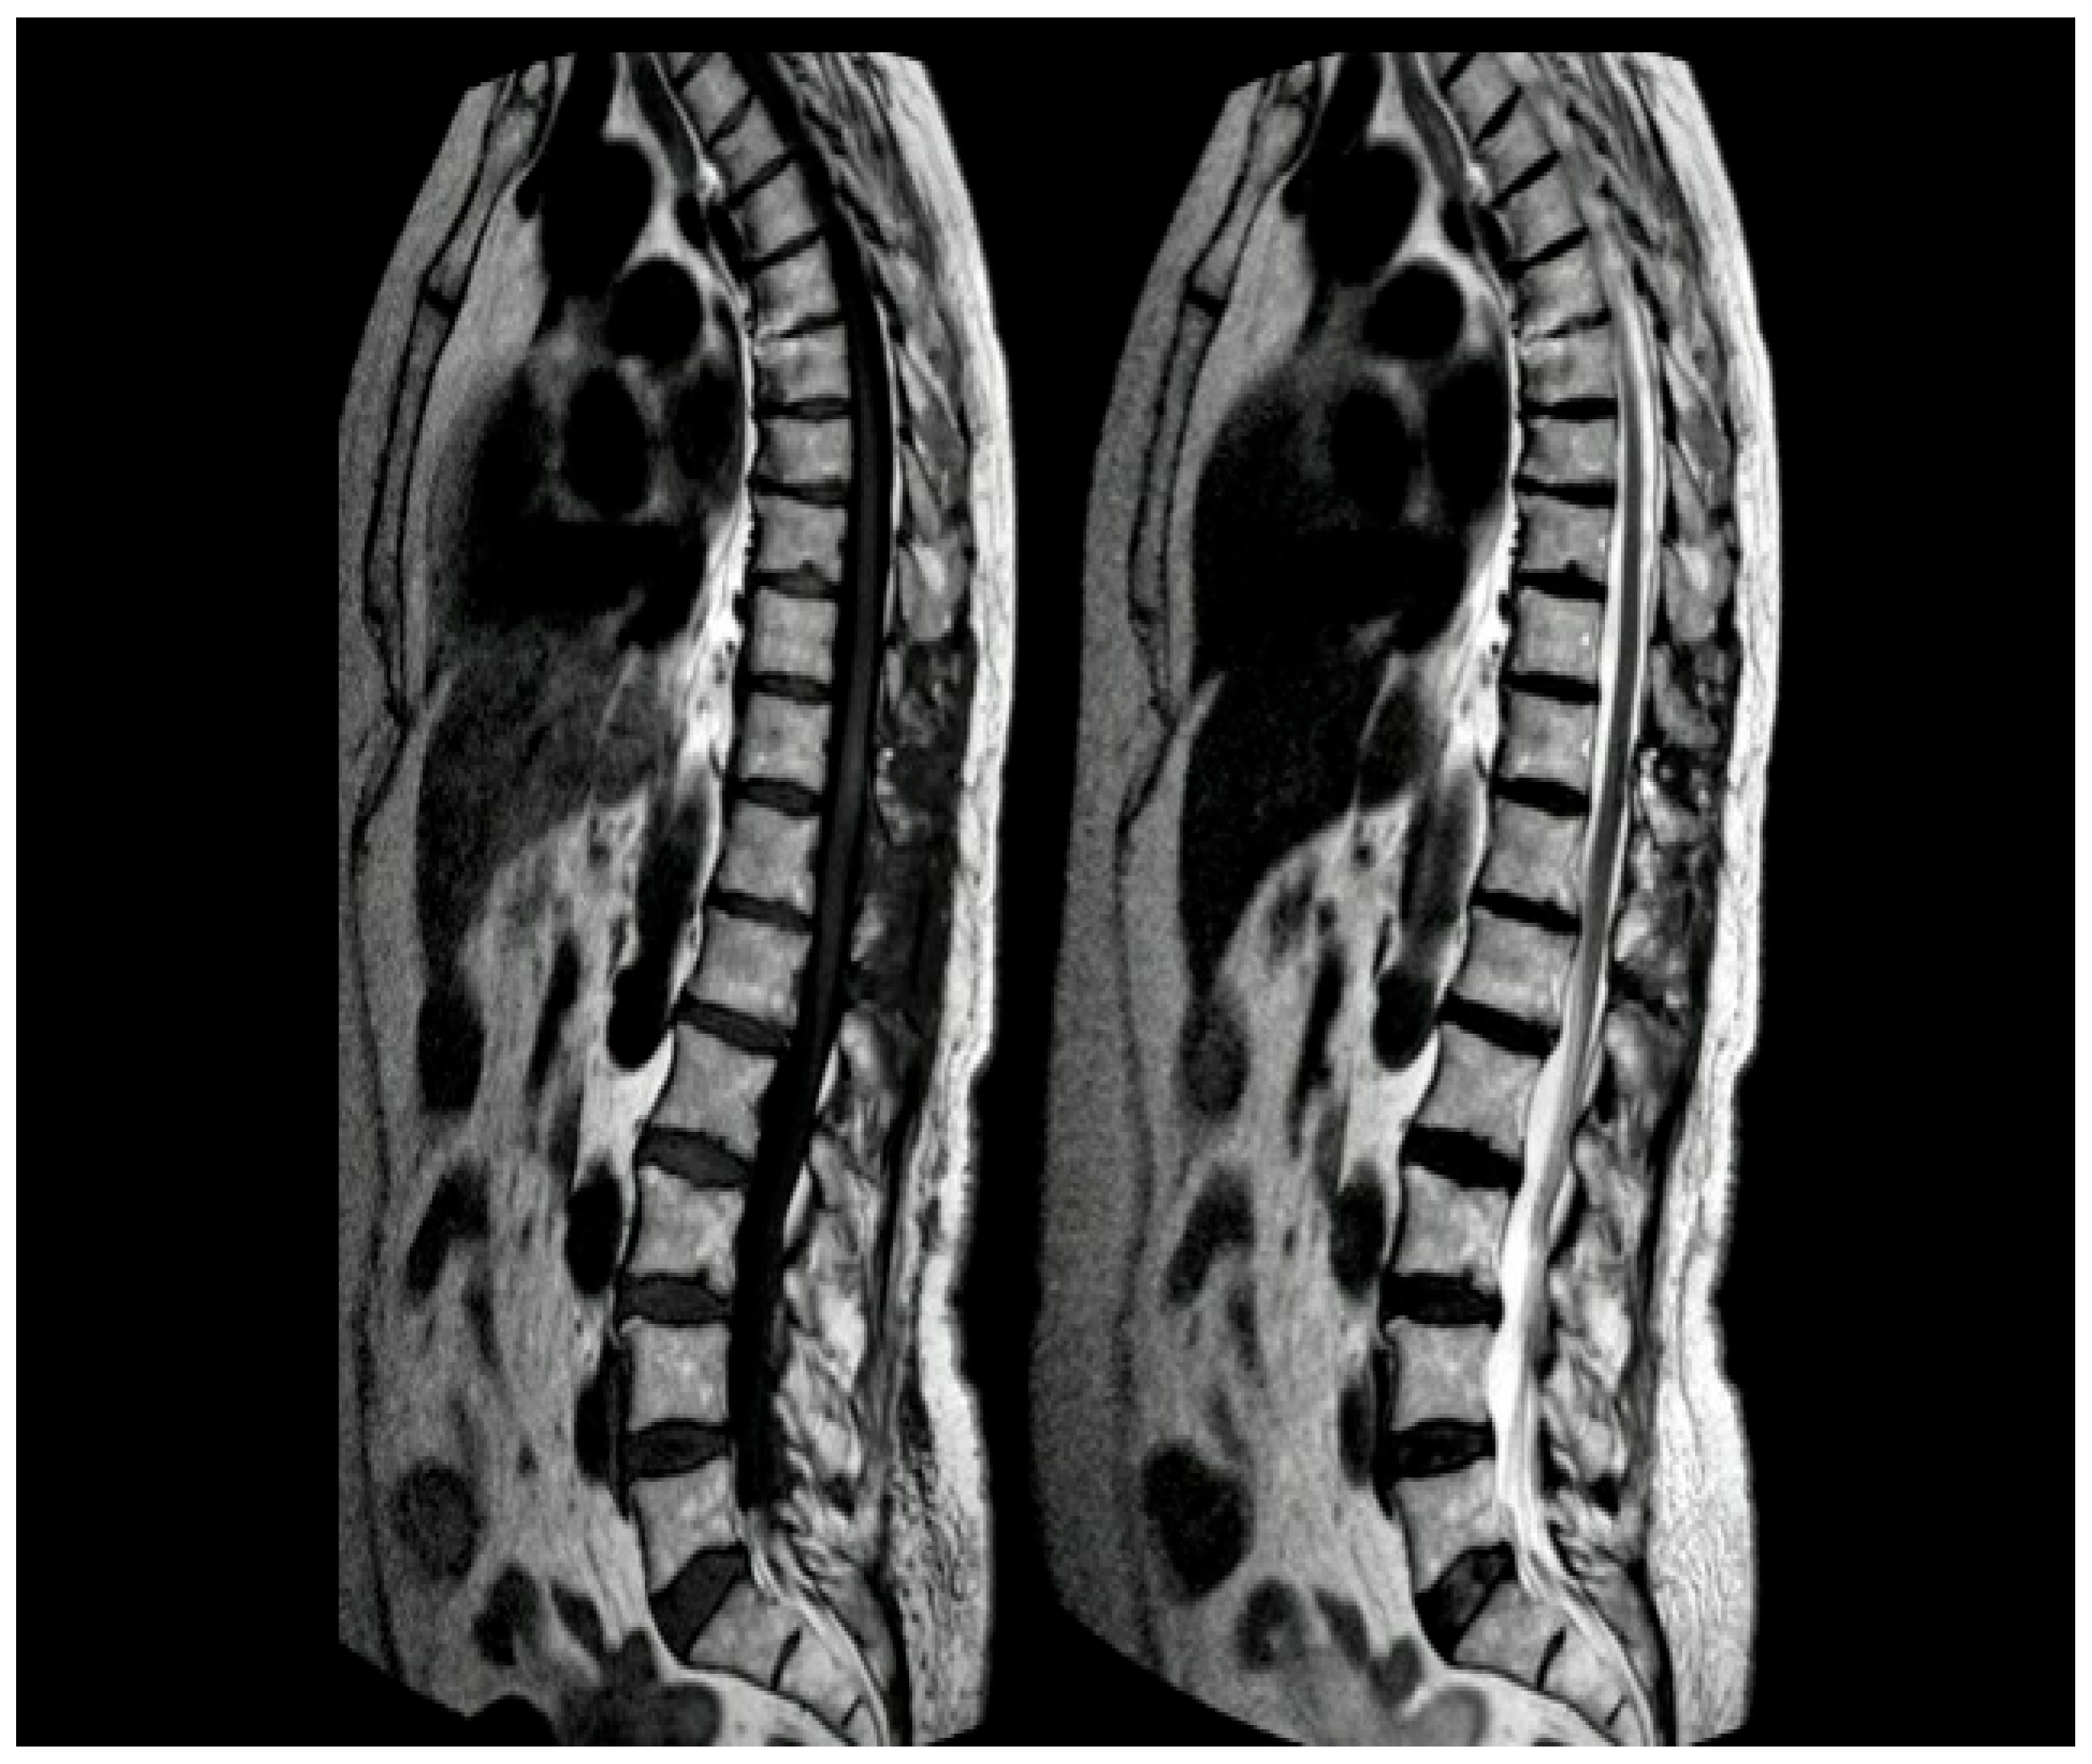

Figure 4.

Intraoperative findings. The hemangioma (red arrow) and arteriovenous fistula (yellow arrow).